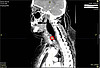

IMG_5289КТ пациентки1

IMG_5289.